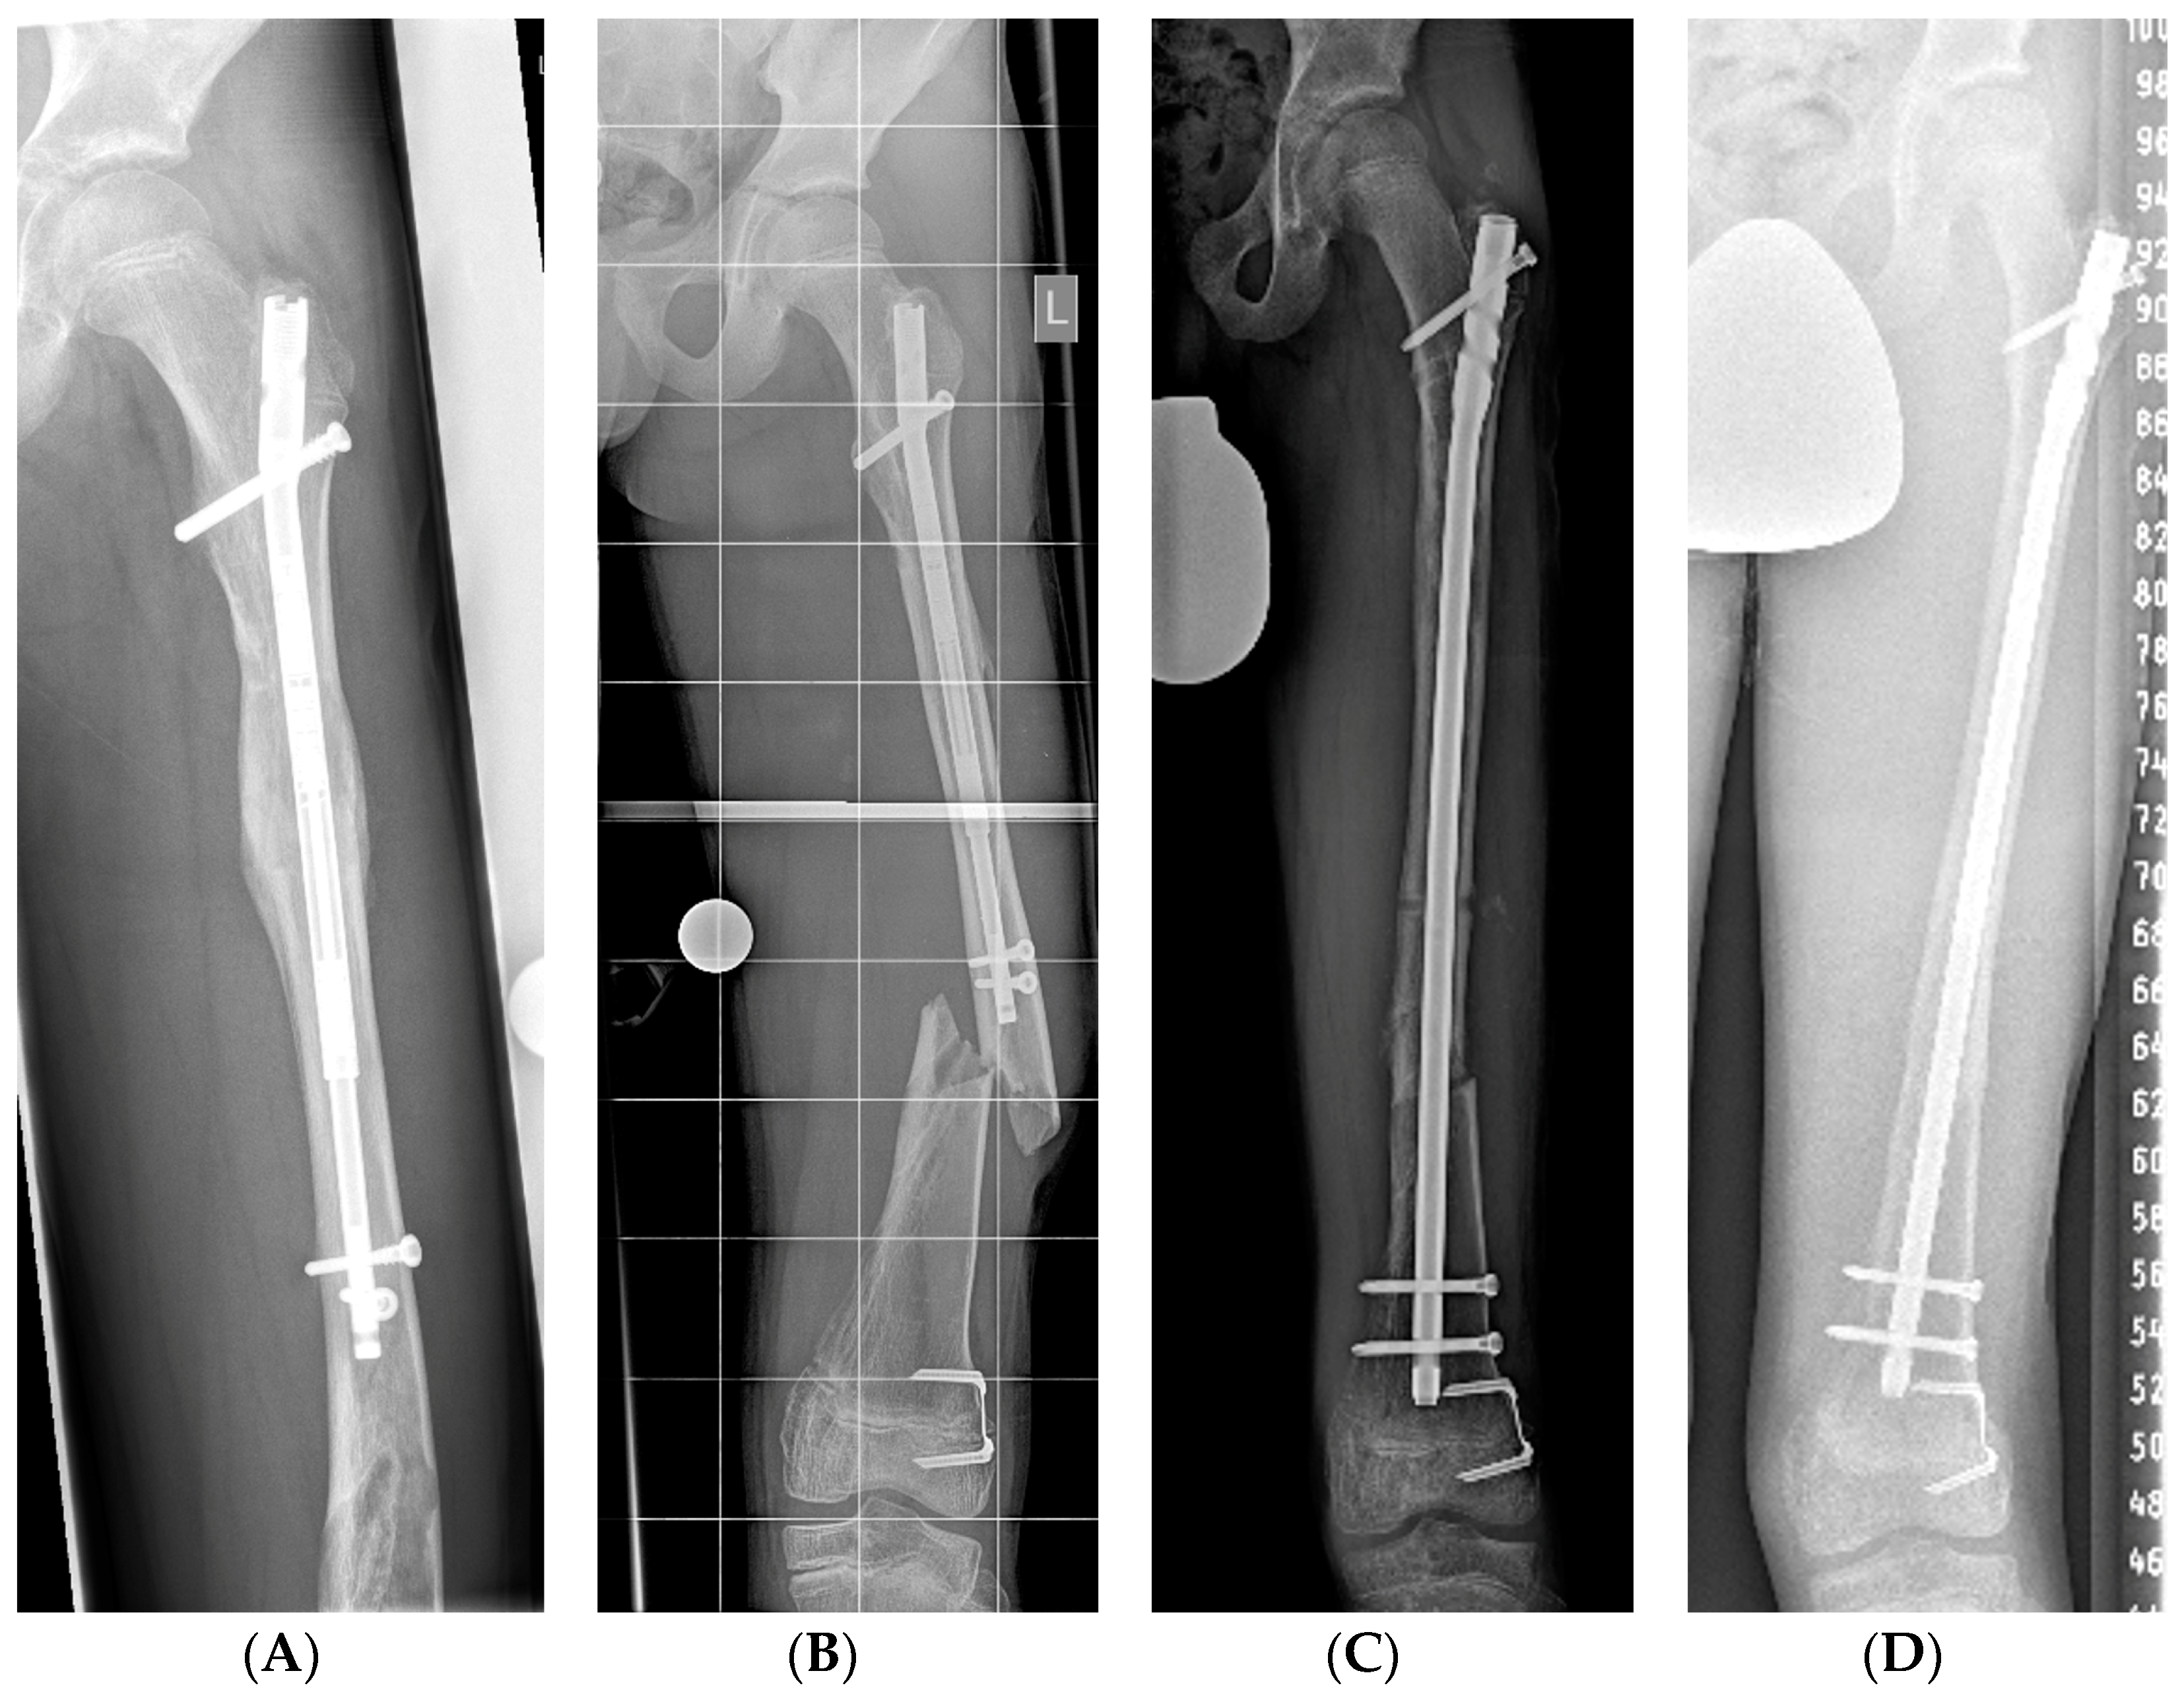

The Future of Intramedullary Limb Lengthening。Motorized Internal Limb Lengthening: An Updated Review。Lower limb lengthening over an intramedullary nail: a long。タイトル Intramedullary Limb Lengthening. Principles and Practice著者 Stuart A. Green Mark T. Dahl書き込み等なく綺麗な状態です。。